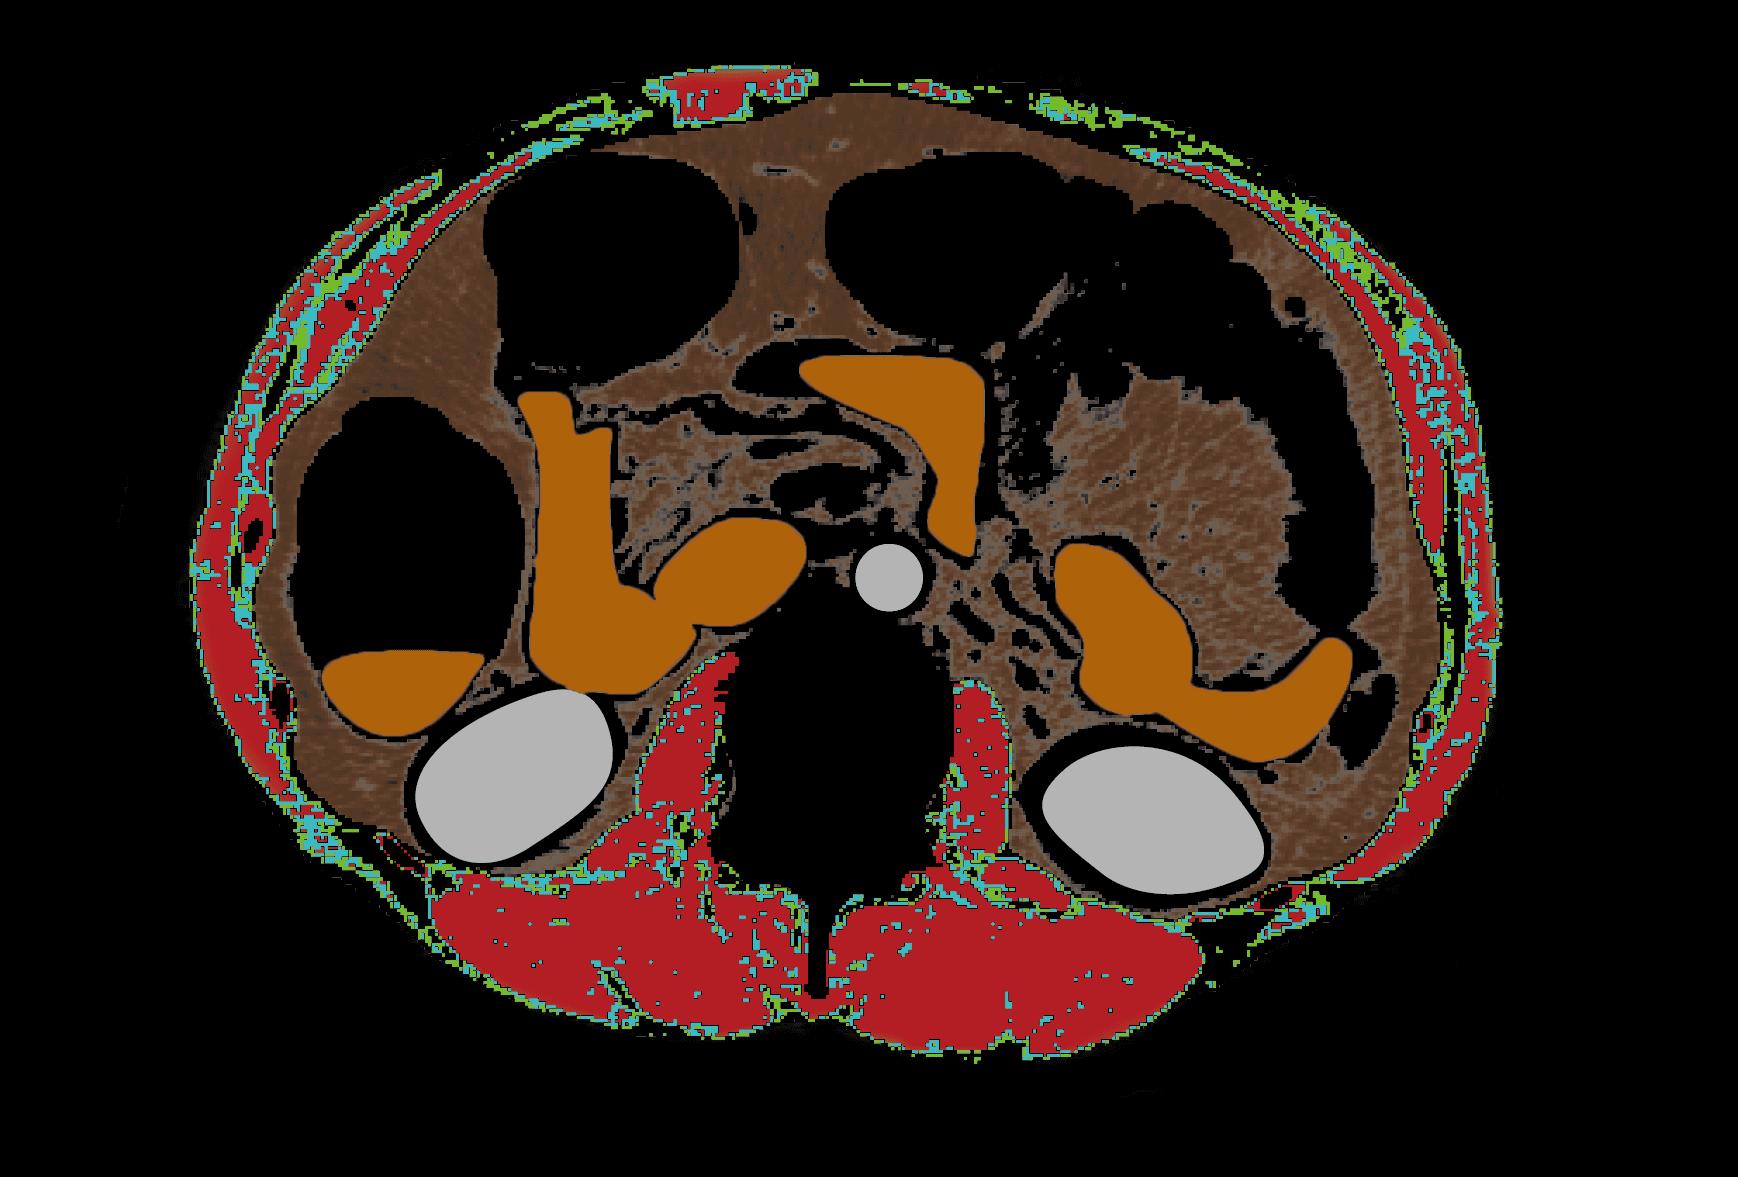

복부둘레근육 분할 성능 96%

우수한 일치도 입증

프로메디우스㈜. 성능 테스트 보고서 (PROS CT-01), 문서번호: PROS-Fuchsia-SPR, 제정일: 2023.05.16, 개정일: 2024.05.10, Rev.1.

NAMA, LAMA, IMAT가 무엇인가요? ¹

1. Kim, Hong-Kyu et al. “Age-related changes in muscle quality and development of diagnostic cutoff points for myosteatosis in lumbar skeletal muscles measured by CT scan.” Clinical Nutrition, Volume 40, Issue 6, 4022 - 4028.